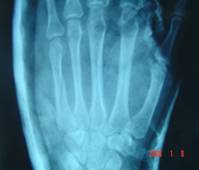

Alcuni dati ci informano di quanto ampia sia la traumatologia della mano: il 10% circa del totale delle fratture del nostro corpo, infatti, è localizzata proprio a livello delle falangi e dei metacarpi.

Questo dato sale drasticamente se se selezioniamo le fratture che coinvolgono solo l’arto superiore, del quale ben l’80% corrisponde alla sua parte terminale. Un secondo dato degno di attenzione è la causa dei traumi: si calcola che tra incidenti sul lavoro e incidenti domestici le fratture coinvolgono la mano si aggirino addirittura attorno alle 500.000 all’anno solo in Italia.. uno dei primi compiti del chirurgo della mano è sicuramente quello di garantire la guarigione delle fratture evitando accuratamente di interferire con la normale guarigione dell’osso. Sia che si decida per un intervento chirurgico che per una riduzione non chirurgica si deve tenere presente la funzionalità definitiva la funzionalità definitiva alla quale si vuole ritornare. La scelta del mezzo di sintesi, quindi, qualora si decidesse per la strada chirurgica, deve essere il più appropriato possibile per riportare la mano alla guarigione, rendendole anche fisiologica la funzionalità. Nelle fratture delle falangi ad esempio una sintesi interna rigida, pur portando ad un ottimo risultato sul paino osseo, potrebbe generare delle difficoltà nello scorrimento tendineo, generando dei fenomeni di rigidità.